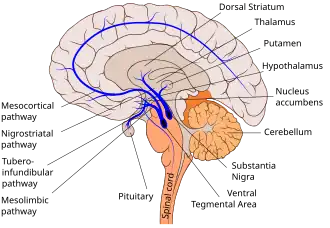

Building on these foundational definitions, this article examines the epigenetic mechanisms which include histone modifications, DNA methylation/demethylation, and microRNA (miRNA) expression. These mechanisms direct neuronal proliferation, differentiation, and integration throughout different life stages. The article begins by outlining embryonic neurogenesis, illustrating how precise histone modifications and DNA methylation patterns govern cortical layer formation. Adult neurogenesis is then explored, specifically regions like the subventricular zone and hippocampal dentate gyrus. This emphasizes how epigenetic factors continue to regulate neural stem cell quiescence, activation, and fate specification.

Additionally, newly included research addresses astrocyte reprogramming, which is the process by which certain glial cells can de-differentiate and assume a neuronal fate. This highlights the critical roles of histone acetylation and DNA methylation in this conversion. A further section explains memory-related genes (e.g., GADD45b) and the importance of epigenetic modifications for learning, synaptic plasticity, and long-term potentiation in the hippocampus. Finally, the article investigates epigenetic dysregulation in various neurological and psychiatric disorders, including Alzheimer's disease, Parkinson's disease, Huntington's disease, and bipolar disorder. In each context, alterations in histone marks, DNA methylation, or miRNA expression disrupt normal neuronal processes, pointing to emerging possibilities for epigenetic therapies.

There are three important methods of epigenetic regulation, which include histone modifications, DNA methylation and demethylation, and microRNA (miRNA) expression. This section of the article explores these mechanisms in detail to understand how they work.

Adult neurogenesis

DNA methylation

Neurogenesis that persists beyond embryonic development and through adulthood is referred to as adult neurogenesis.[14] An important animal gene involved in the epigenetic regulation of adult neurogensis is the Growth arrest and DNA-damage-inducible, beta (GADD45b) gene, often studied in rodents like mice.[15] Through the demethylation of promoters, GADD45b activates genes such as brain-derived neurotrophic factor (BDNF) and basic fibroblast growth factor (FGF2)[16] which are essential for neural progenitor cell development. Consequently when there is an upregulation of GADD45b, there is increased expression of BDNF and FGF2 resulting in more neural progenitor cells in adulthood.[1][16]

Histone Acetylation in Neural Stem Cell Regulation

DNA is packaged into chromatin, a structure made up of nucleosome subunits consisting of four histone proteins H2A, H2B, H3 and H4. Both histone acetylation and deacetylation play a role in the proliferation and self-renewal of post-embryonic neural stem cells. In the absence of acetylation, H4 histones retain their basic charge, allowing them to interact with the acidic pockets of H2A-H2B dimers in neighboring nucleosomes. This interaction reinforces nucleosome-nucleosome association, resulting in more tightly packed chromatin. Acetylation neutralizes the basic charge of H4 histones, disrupting these interactions and thereby preventing chromatin compaction.[17] This process allows for greater expression of target genes like brain-derived neurotrophic factor which are involved in adult neurogenesis. Acetylation is made possible by histone acetyltransferases (HATs), which add acetyl groups to histones, promoting gene expression by loosening chromatin structure. Conversely, histone deacetylases (HDACs) remove acetyl groups, leading to chromatin condensation and gene repression. Histone acetylation plays a key role in the differentiation of nerual stem cells into specific cell types. A notable example is the chromatin regulator BRPF1, which is abundantly expressed in the developing central nervous system. It is crucial for the formation of brain regions such as the neocortex and dentate gyrus of the hippocampus. BRPF1 functions by activating histone acetyltransferases like MOZ, MORF, and HBO1,[18] which drive histone acetylation processes essential for proper neural development.

Role of HDAC Inhibitors in Promoting Neurogenesis

Histone deacetylase inhibitors (HDACi)—such as valproic acid (VPA) and trichostatin A—can enhance adult neurogenesis by blocking HDAC activity, which promotes the differentiation of adult neural progenitor cells.[19] In neural stem cells, HDAC1 and HDAC2 work with the transcription factor TLX to suppress genes that limit cell proliferation, including the cell cycle inhibitor P21 and the tumor suppressor Pten.[20] This repression supports the self-renewal and proliferation of neural stem cells. However, when HDACs are inhibited—such as by VPA, an antiepileptic drug—it can shift neural stem cells toward neuronal differentiation. Similar to processes seen in embryonic neurogenesis, VPA can also suppresses glial cell differentiation in adult neural stem cells. This effect is likely driven by the upregulation of neuron-specific genes, including neurogenic basic helix-loop-helix (bHLH) transcription factors like NEUROD, NEUROGENIN1, and MATH1. While HDAC inhibition can promote neurogenesis, complete loss of HDAC1 and HDAC2 in neural progenitor cells has the opposite effect, potentially preventing proper neuronal differentiation. Similarly, their loss in oligodendrocyte progenitor cells disrupts oligodendrocyte formation, highlighting that histone deacetylation plays distinct and essential roles at various stages of neural development.

MicroRNAs and Post-Transcriptional Regulation of Neurogenesis

MicroRNAs (miRNAs) are small noncoding RNAs that regulate gene expression at the post-transcriptional level, controlling protein production without altering the DNA sequence. One important microRNA in adult neurogenesis is miR-9, which plays a crucial role in cell differentiation.[21] miR-9 targets the nuclear receptor TLX in adult neurogenesis to promote neural differentiation and inhibit neural stem cell proliferation. It also influences neuronal subtype specification and regulates axonal growth, branching, and targeting in the central nervous system through interactions with HES1, a neural stem cell homeostasis molecule.

Another crucial miRNA in adult neurogenesis is miR-124, which promotes cell cycle exit and neuronal differentiation. Several mouse studies have shown that ectopic expression of miR-124 leads to premature differentiation and depletion of neural progenitor cells in the subventricular zone (SVZ), a major adult neurogenic region lining the lateral ventricles.[22] The SVZ continuously generates neuroblasts that migrate to the olfactory bulb, and miR-124 overexpression disrupts this process by forcing early cell cycle exit, ultimately reducing long-term neurogenesis. In addition to miR-9 and miR-124, other miRNAs play essential roles in regulation of adult neurogenesis. miR-137, miR-184 and miR-195 regulate adult neural stem cell proliferation, with their over-expression leading to up-regulated proliferation while their down-regulation leads to a decrease in neuronal proliferation.[23] Methyl-CpG binding protein 1 (MBD1) represses miR-184, a microRNA that promotes the proliferation of adult neural stem/progenitor cells (aNSCs) while inhibiting their differentiation by targeting and downregulating Numblike (Numbl), a protein involved in promoting neuronal differentiation. In adult neurogenesis, MBD1, miR-184, and Numbl function together to balance stem cell maintenance and neuronal output. Similarly, miR-195 forms a negative regulatory loop with MBD1; its inhibition promotes aNSC differentiation, and its levels naturally decrease as differentiation proceeds.[24] Disruptions in MBD1 or miRNA signaling have been linked to neurodevelopmental disorders, mood disorders, and impaired cognitive function, all of which underscore the importance of finely tuned adult neurogenesis.

Epigenetic dysregulation and neurological disorders

Epigenetic dysregulation, or alterations in epigenomic machinery, can cause DNA methylation and histone acetylation processes to go rogue. The epigenetic machinery influences neural differentiation regulation (i.e. neurogenesis)[36] and are also involved in processes related to memory consolidation and learning in healthy individuals.[37] DNA methylation and histone modifications play a critical role in modulating gene expression related to synaptic plasticity, which is essential for learning and memory formation.[32] Increasing age can produce various epigenetic changes such as reduced global heterochromatin, nucleosome remodeling, altered histone marks, and changes in DNA methylation. For instance, nucleosome loss occurs due to aging because core histone proteins are lost and less protein synthesis occurs.[38] Epigenetic control of enhancer regions in neurons has been linked to neurodegenerative diseases, particularly Alzheimer's disease, where dysregulated chromatin accessibility contributes to neuronal dysfunction.[39] Notably, chromatin loops that regulate enhancer-promoter interactions appear to be disrupted in neurodegenerative conditions, leading to widespread transcriptional alterations. As aging is the main risk for many neurological disorders, epigenetic dysregulation can in turn lead to alterations on the transcriptional level of genes involved in the pathogenesis of neural degenerative diseases such as Parkinson's disease, Alzheimer's disease, Huntington's disease, schizophrenia, and bipolar disease.[1][40]